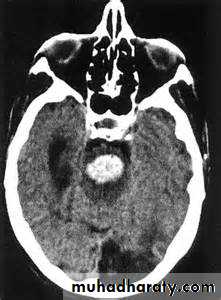

the principle imaging for ICH is CT scanning

Conventional T1 and T2 sequences are not highly sensitive to hemorrhage in the first few hours, but newer gradient refocused echo sequences appear to be able to detect intracerebral hemorrhage reliably within the first 1-2 hours of onset (MRI studies incorporating gradient echo or susceptibility-weighted sequences may be used as the sole imaging modality for patients with acute stroke, readily identifying intracranial hemorrhage• Vessel imaging